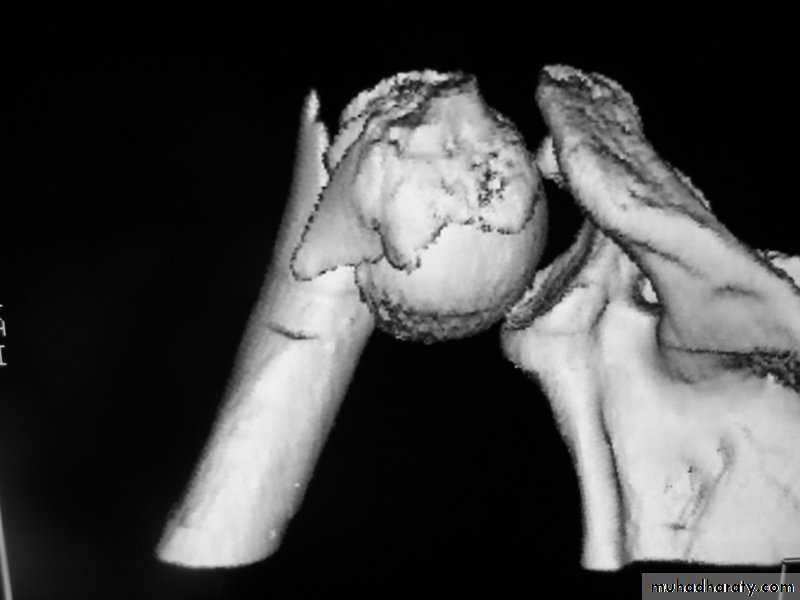

3-D reconstructed images.

3-D C-T in fracture pelvic ilium